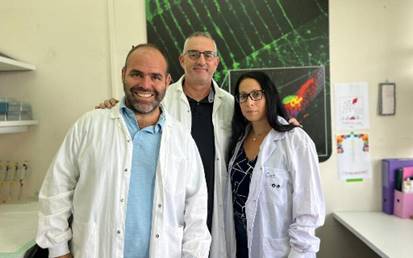

Añadiendo una molécula específica de microARN a modelos celulares de humanos y de animales de ELA, investigadores de la Universidad de Tel Aviv—en colaboración con la Universidad Ben-Gurión, el Instituto Weizmann y centros de Francia, Turquía e Italia—reportan que las neuronas motoras deterioradas detuvieron su degeneración e incluso mostraron signos de regeneración.

El estudio, publicado recientemente en Nature Neuroscience, fue coordinado por el profesor Eran Perlson (Facultad Gray de Ciencias Médicas y de la Salud, Universidad de Tel Aviv), quien explicó: “Cuando añadimos una molécula de ARN específica a células humanas y a modelos animales de ELA, las células nerviosas dejaron de degenerarse e incluso se regeneraron”.